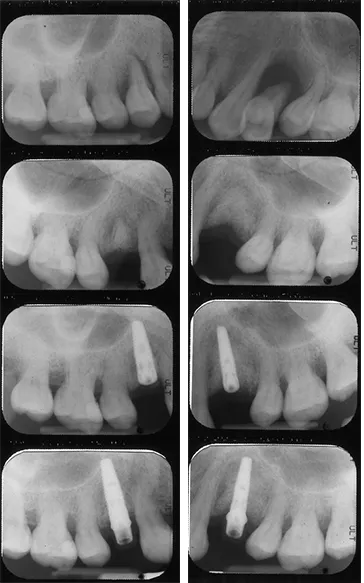

Dental Implant and Ridge Augmentation

Ridge modification is an effective procedure for treating deformities in the upper and lower jaws.  These deformities can occur as a result of periodontal disease, trauma, injury, wearing dentures, or developmental problems.  Such defects can leave insufficient bone for the placement of dental implants and an additional unattractive indentation in the jaw line adjacent to the missing teeth.

During the ridge modification procedure, the gum is lifted away from the ridge to fully expose the defect in the bone.  The bony defect can be filled with bone graft material which can help regenerate lost bone, or a bone substitute.  Finally, the incision is closed and several months of healing will be required.  Depending on the case and type of implant and procedure, a dental implant may be placed during the ridge modification procedure or when healing is complete; much depends on the precise condition of the bone.  Ridge modification improves the cosmetic appearance, functionality of the mouth, and the chance of enjoying dental implants for many years.

Before & After